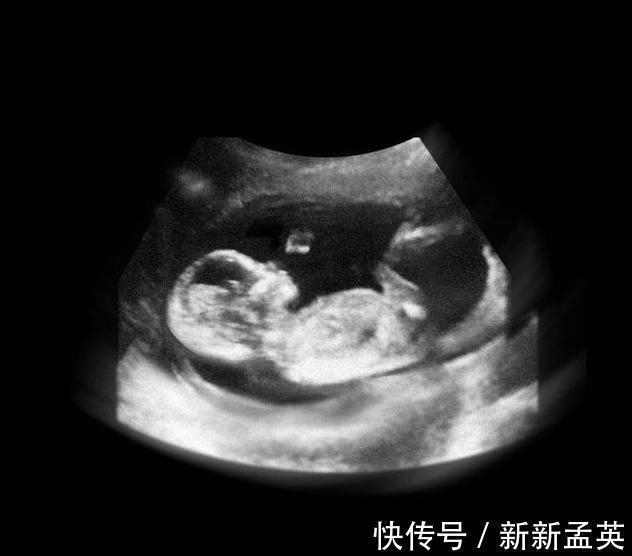

进入12周,胎儿开始在羊水中又动了,骨骼发育开始坚硬,宝宝的四肢开始做很多动作,肾脏开始分泌尿液,肝脏开始分泌胆汁,维持生命的重要器官更多地开始工作了。